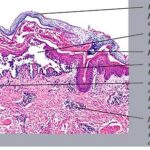

Histopathology. Although, as in Darier’s disease, early lesions may show small suprabasal separations, so-called lacunae, fully developed lesions show large separations, that is, vesicles and even bullae, in a predominantly suprabasal position . Villi, which are elongated papillae lined by a single layer of basal cells, protrude upward into the bulla, and in some cases, |

narrow strands of epidermal cells proliferate downward into the dermis. Many cells of the detached stratum malpighii show loss of their intercellular bridges; thus, acantholysis affects large portions of the epidermis. |

Individual cells and groups of cells usually are seen in large numbers in the bulla cavity. Despite the extensive loss of intercellular bridges, the cells of the detached epidermis in many places show only slight separation from one another, because a few intact intercellular bridges still hold them loosely together. This quite typical feature gives the detached epidermis the appearance of a dilapidated brick wall. |

Differentiation of familial benign pemphigus from Darier’s disease as a rule is not very difficult, because in Darier’s disease, the suprabasal separations usually are smaller, thus appearing as lacunae rather than as bullae; acantholysis is less pronounced, being limited to the lower epidermis, especially the suprabasal region; and dyskeratosis consisting of the formation of corps ronds and grains is much more evident. |

Pemphigus vulgaris often resembles familial benign pemphigus to a striking degree, and in some specimens, histologic differentiation of these two diseases may be impossible. As a rule, however, there is less extensive acantholysis in pemphigus vulgaris, limited largely to the suprabasal region, so the detached epidermis appears normal and lacks the appearance of a dilapidated brick wall, and more severe degeneration of the acantholytic cells within and near the bulla cavity. The presence of eosinophils in the bulla points toward a diagnosis of pemphigus vulgaris, but their absence does not rule it out. In case of doubt, immunofluorescence will decide the issue. |

Differential Diagnosis. Histologically, familial benign pemphigus shares certain features with both Darier’s disease and pemphigus vulgaris. In all three diseases, one finds predominantly suprabasal separation of the epidermis caused by acantholysis and resulting in lacunae or bullae and villi formation. |